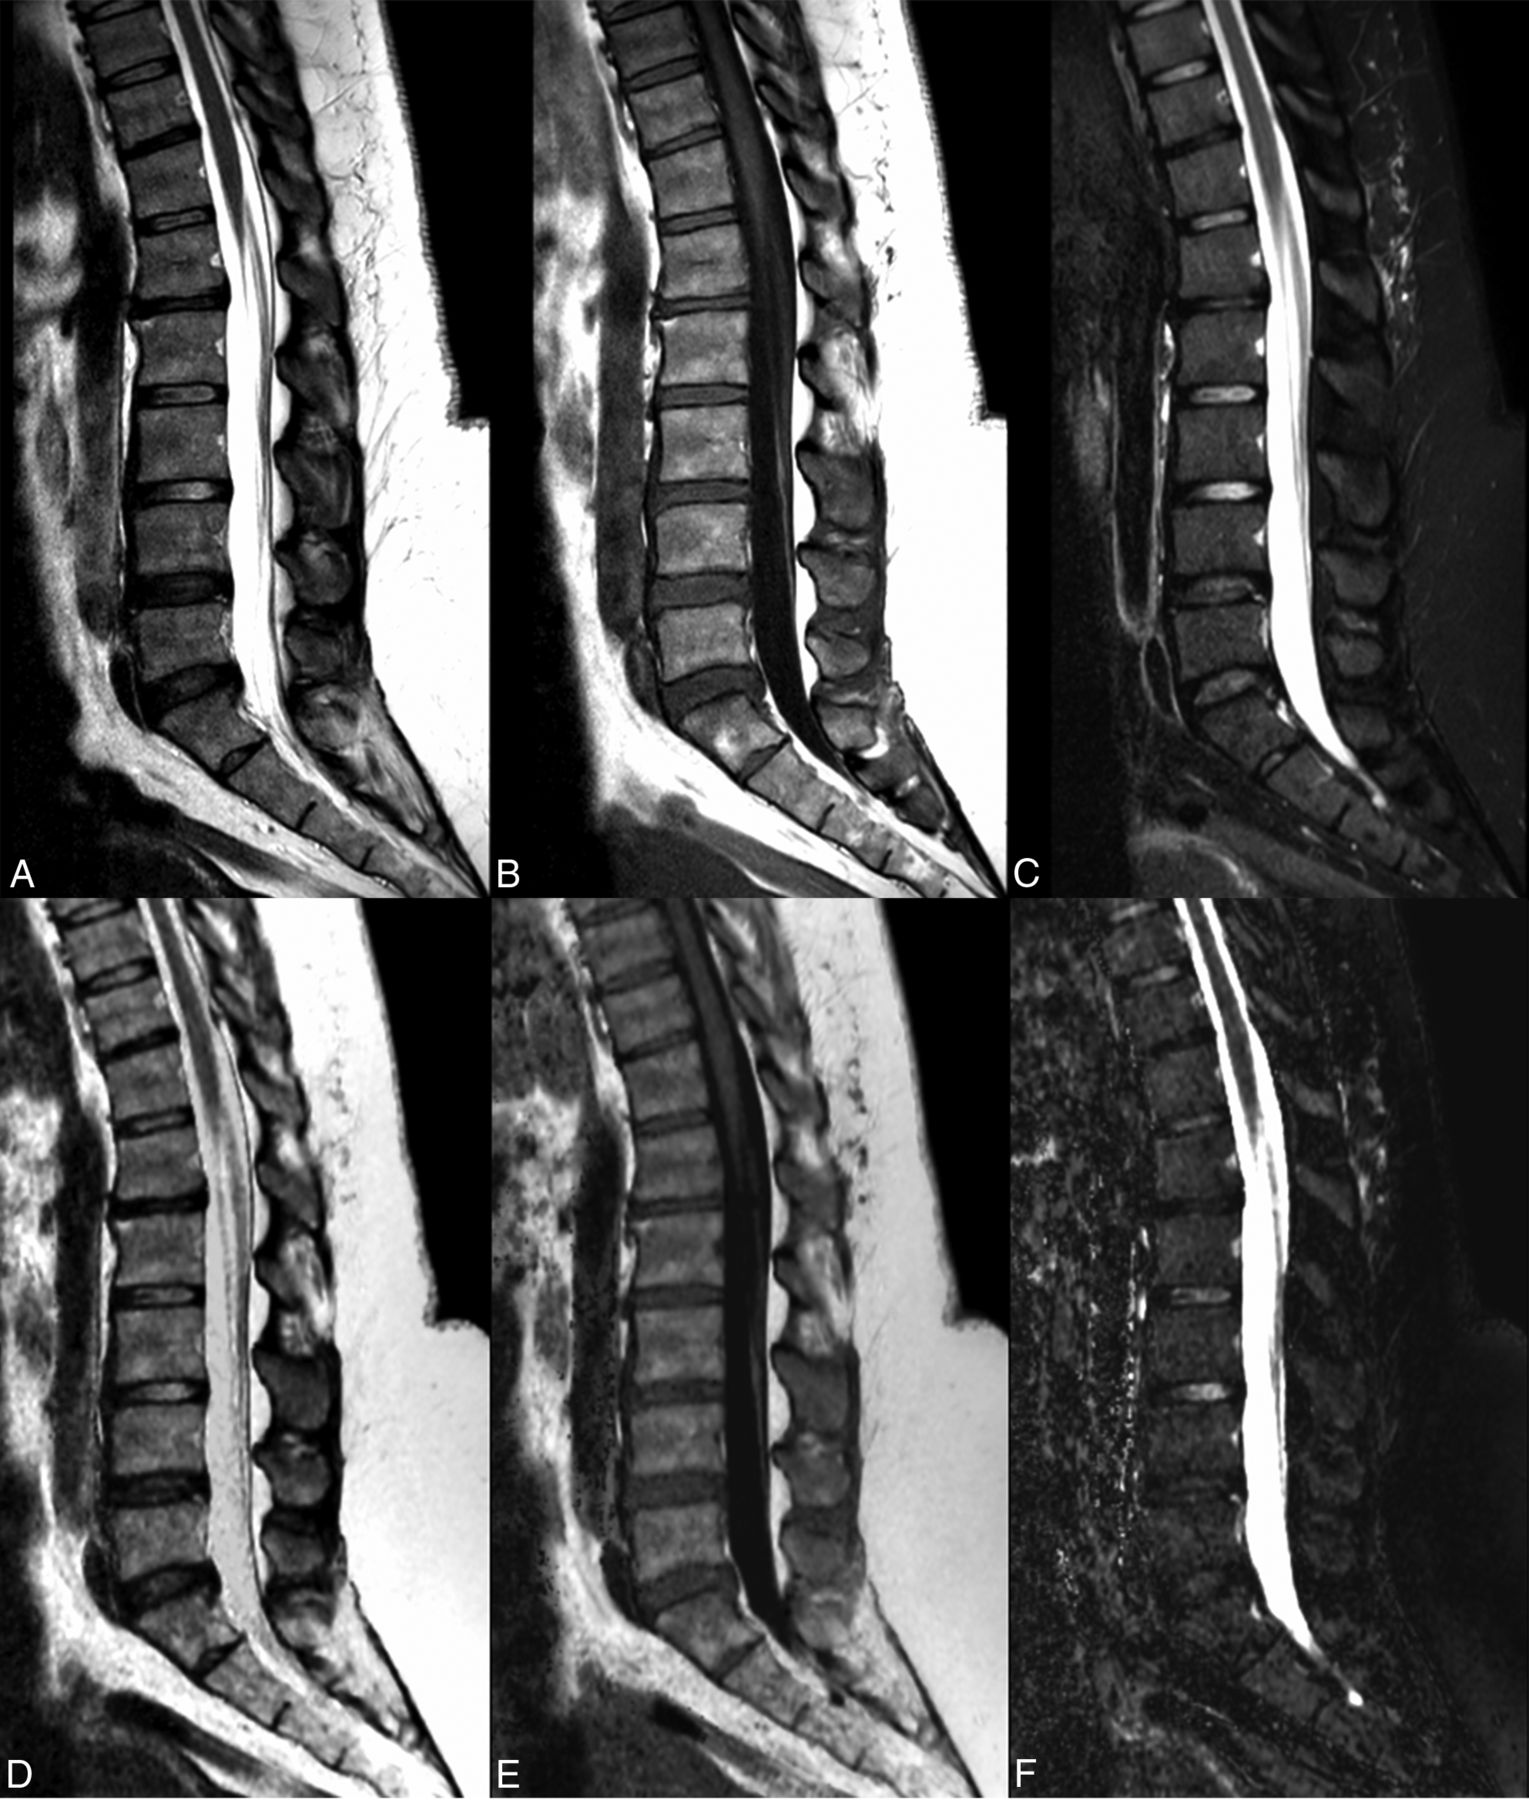

Artifacts consisting of white pixels/spike noise across contrast views and flow artifacts were more common in the synthetic sequences (except proton-density), especially in synthetic STIR (Fig 3).

Conventional FSE T2 (A), spin-echo T1 (B), and STIR (C) images show a postsurgical lumbar spine with postoperative changes in the posterior soft tissues. The synthetic images (D–F) depict these changes with similar detail. Note the dirty appearance of the vertebral bodies observed in the synthetic reconstructions and flow artifacts from the aorta, especially in the synthetic STIR sequence.